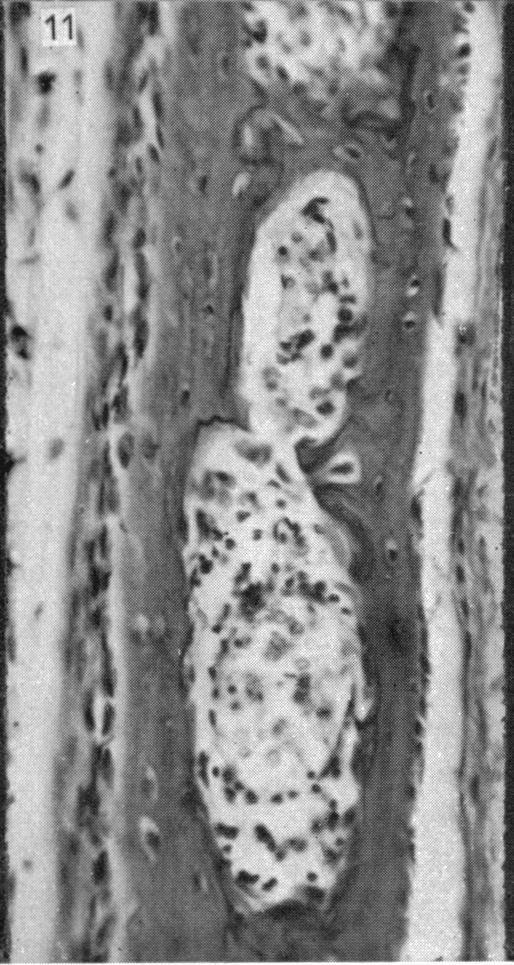

Alizarin as an indicator of bone growth.

J Anat. 1960 Jul;94(Pt 3):432-42.